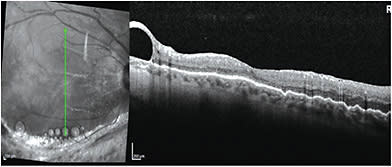

Pastor et al. showed that PFO has a toxic effect on the human retinal pigment epithelial (RPE) cells (ARPE-19).4 Elsing et al. also showed that histopathologic analysis of five eyes with retained PFO after vitreoretinal surgery for retinal detachment revealed an inflammatory response.5 This inflammatory response consisted mainly of macrophages with intracellular vacuoles containing PFO. However, removal of the PFO in all five eyes resulted in the resolution of the inflammatory response.5 Given the toxic effect of PFO on RPE and loss of retinal functions, subfoveal or sub-juxtafoveal PFO is often removed.6 However, sub-extramacular or subperipheral retina PFO does not result in a negative functional or anatomical outcome, and may be safely left alone2 (Figure 1).